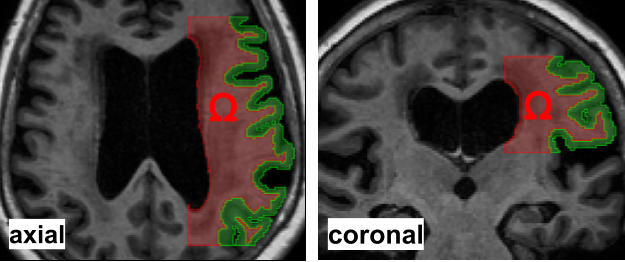

Our workflow to solve this problem on MRI data is illustrated in Fig. 1. Figure 2(a) illustrates the white matter subregion we consider in this work. Figure 2(b) shows a slice view of the concentration after 24 hours for the three datasets considered in this work, i.e., MRI data, synthetic data with and without noise. In all cases, we use data at hours (after tracer injection at ).

We next use FreeSurfer [30] to segment the baseline image into anatomical regions and obtain binary masks for white and gray matter. The human brain has many folds and represents a highly complex geometry. To limit the intrinsically high computational requirements of inverse problems, we focus on a subregion of the white matter shown in main Fig. 2(a).